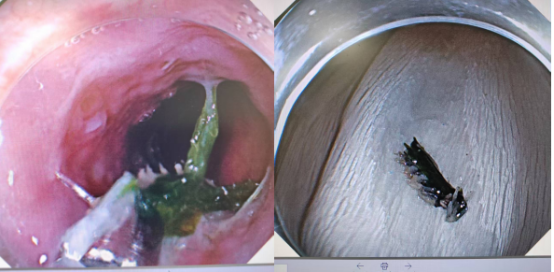

此時的郭女士情緒極不穩(wěn)定,醫(yī)護(hù)人員一邊耐心安撫,一邊迅速為她進(jìn)行檢查。胃鏡下,我們清晰地看到那根罪魁禍?zhǔn)?/span>——泥鰍刺,正牢牢嵌頓在食管上段。

消化內(nèi)科和內(nèi)鏡中心醫(yī)護(hù)人員的密切配合,精準(zhǔn)無誤地將這枚泥鰍刺取出,手術(shù)過程十分順利,異物被成功取出。術(shù)后患者癥狀即刻緩解。